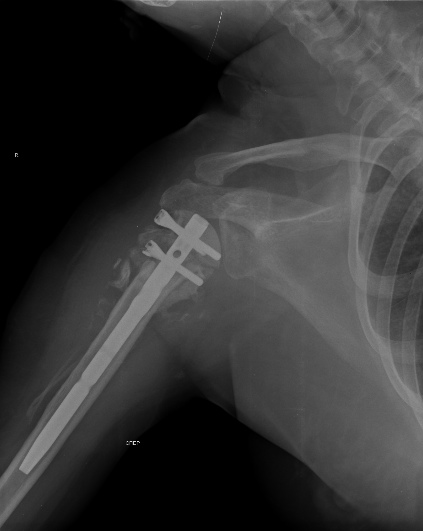

Пошли на операцию, будучи готовыми как к фиксации, так и к протезированию. Головка с краев была неполная, но для двух винтов места хватило. Сделали что-то вроде гемиартропластики собственной головкой. Бугорки фиксировали, как при эндопротезировании.

Снимки вот.

The nail looks a little proud. Will it not come in the way of mobilisation of the shoulder? What is your postop protocol in this case?

But if I should act as the devil’s advocate, I suppose, actually hope, the head was not totally avascular, there is some graft added, there might be either some faint impingement of the most proximal screw against the acromion or even the nail is a little proud cranial the bone ( or even the cartilage ? ). Maybe the end could be an avascular necrosis and it might be well tolerated ! Lots of bad possible outcomes and some possitive one.

действительно интересен протокол послеоперационного ведения и почему выбран несколько нетрадиционный способ фиксации? В случае закрытой операции преимущества есть, а здесь? Пластина более адекватна, как кажется, как минимум из-за количества винтов? Согласен с мнением коллеги по поводу костной пластики: bone stock и ! офсет, что может быть неплохо при непонятной неврологии.

Ты нашу тактику знаешь, мы бы поставили пластину. Хотя без пластины, но получилось здорово!

Там видно ты применил Синтезовский MultiLoc гвоздь с screw in screw технику. Главное, ты собрал фрагменты и если понадобится следующие операции, тогда будет легче...